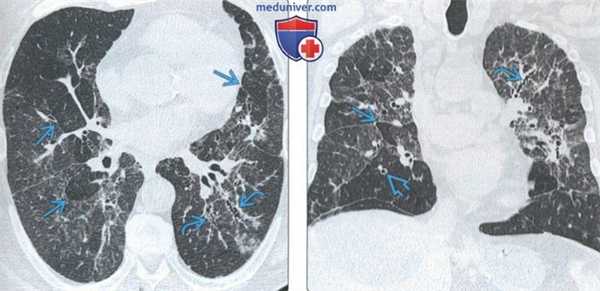

(Слева) На аксиальной КТВР у пациента с перибронхиальным интерстициальным фиброзом определяется утолщение перибронхиальных тканей наряду с деформацией бронховаскулярных пучков и «мозаичной» картиной легочной ткани.

(Справа) На аксиальной экспираторной КТВР у этого же пациента определяется «географическая» или «мозаичная» картина, обусловленная заболеванием периферических дыхательных путей. Обратите внимание на небольшой диаметр легочных сосудов в участках со сниженной плотностью. Наиболее типичными причинами перибронхиального интерстициального фиброза являются гиперчувствительный пневмонит и гастроэзофагеальная рефлюксная болезнь. (Слева) На аксиальной КТВР у пациента с перибронхиальным интерстициальным фиброзом определяется утолщение перибронховаскулярных тканей на фоне тракционных бронхоэктазов и слабо выраженной «мозаичной» картины. Обратите внимание на воздушные «ловушки» в пределах легочных долек.

(Справа) На корональной КТ без КУ у этого же пациента визуализируются множественные участки «матового стекла» с преимущественно перибронховаскулярной локализацией. Обратите внимание на асимметричную «мозаичную» картину и очаги в виде «дерева в почках» в верхней доле правого легкого на ограниченном участке.